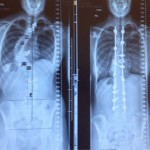

- Omurga düzeltme ameliyatı öncesi ve sonrası